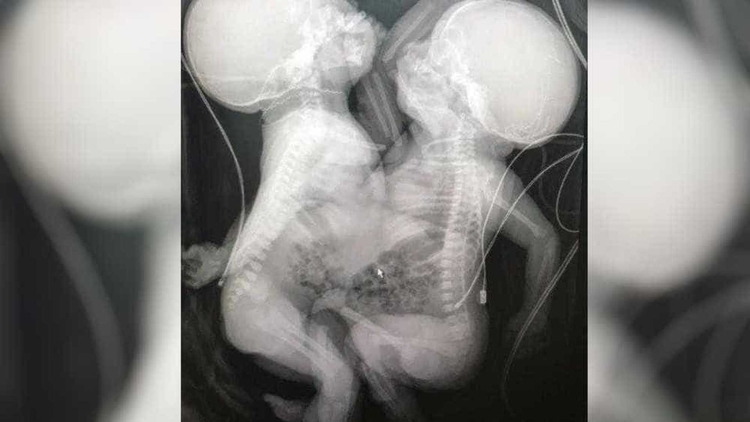

Duas crianças siamesas que passaram por uma cirurgia de separação na última quarta-feira (23) em Goiânia, estão em estado gravíssimo no Hospital Materno Infantil (HMI).

Segundo os médicos, as meninas que nasceram unidas pelo tórax e compartilhavam o mesmo fígado foram submetidas a uma cirurgia de urgência, porque uma delas apresentava um problema grave no coração e precisaria passar por outro procedimento.